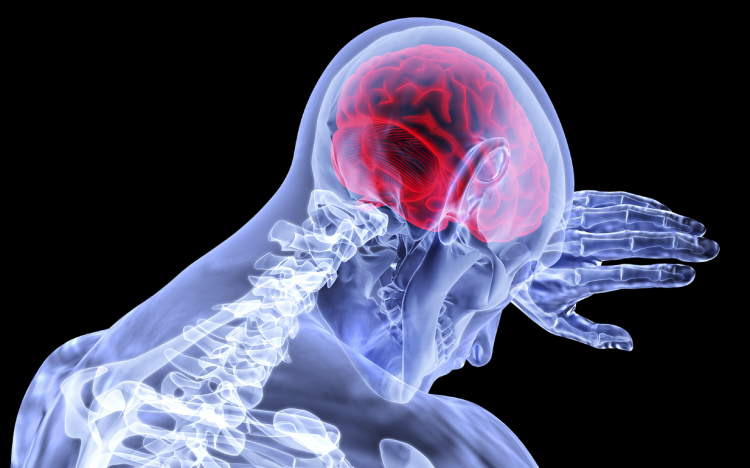

Egy új kutatás szerint mégsem fertőzi meg az agysejteket a koronavírus

Egy új kutatás szerint az új típusú koronavírus (SARS-CoV-2) mégsem fertőzi meg az emberi agysejteket.

A Cell című tudományos folyóiratban közölt tanulmány eredményei reményt keltenek, hogy a korábban véltnél felszínesebb, valamint helyreállítható a vírus okozta neurológiai károsodás - olvasható a The Guardian című brit napilap online kiadásában.

A kutatás ellentmond a korábbi munkáknak, amelyek szerint a vírus az orr felső mélyedéseiben lévő nyálkahártya neuronjait fertőzi meg, belégzéskor ide érkezik a kórokozó. A hártyán lévő szaglósejtek (OSN) teszik lehetővé az illatok érzékelését. Szorosan együttműködnek az úgynevezett szusztentikuláris sejtekkel, amelyek a szaglósejtek munkáját segítik.

A belga és német kutatók munkája arra utal, hogy a vírus a szusztentikuláris sejteket fertőzi meg, a szaglósejteket nem.

"Alapvető a különbség. Ha a szaglósejtek megfertőződhetnek, innen rövid az út a szaglógumóhoz, onnan az agyba" - mondta Peter Mombaerts, a német Max Planck Intézet frankfurti Neurológiai kutatóközpontjának vezetője.

Az agyban lévő szaglógumó az a hely, ahol az illatok idegi ingerületeit először feldolgozzuk. Ha a vírus ide behatolna, elméletileg az agy mélyebb rétegeibe is eljuthatna, ahol tartós károsodást okozna, különösen azért, mert a szaglósejtekkel ellentétben a legtöbb neuron nem regenerálódik.

Ha azonban a vírus a szusztentikuláris sejteket fertőzi meg, a károsodás rövidebb ideig tart. Mindkét útvonal magyarázhatja a szaglásvesztést, amely az új típusú koronavírus okozta Covid-19 pácienseinek nagyjából felét érinti. Közülük minden tizedik hosszú távon, talán örökre elveszti a szaglását.

A kutatócsoport megvizsgálta a Covid-19 más idegrendszeri tüneteit, köztük a fáradtságot és az úgynevezett agyi ködöt. Nem vonják kétségbe, hogy a betegség érinti a központi idegrendszert, a vita arról szól, hogy a hatások azért lépnek-e fel, mert a vírus megfertőzi az idegsejteket, vagy valamilyen közvetett mechanizmus áll a tünetek mögött.

A kutatók új technológiával tanulmányozták az idegrendszeri károsodásokat: agyalapi sebészettel vettek mintát a szaglóidegsejtekből és a szaglógumóból a kór következtében elhunyt betegektől, haláluk után nagyjából egy órán belül. 30 páciensnél állapították meg, hogy a vírus még mindig szaporodik, ami azt jelenti, hogy a betegség fertőző, akut szakaszában okozott halált. A 30 elhunyt közül csak hatnál találták meg a vírust a szaglóhártyában.